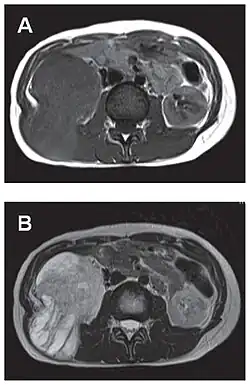

L'imagerie par résonance magnétique permet une exploration complémentaire dans certaines localisations. Elle est surtout réalisée pour les tumeurs du système nerveux central[8],[12],[43], du foie et du pelvis[31],[41]. Elle évalue mieux les différences de densité intra-tumorale et permet d'affirmer l'absence d'envahissement des tissus mous et des structures osseuses voisines[20]. Les tumeurs fibreuses solitaires ont un aspect d'isosignal en séquence T1 et d'hypersignal en T2, et se rehaussent après l'injection de gadolinium[31]. Cependant, dans le système nerveux central, elles ne présentent pas de critères caractéristiques permettant de poser un diagnostic de manière uniquement radiologique[12] et, en pré-opératoire, sont souvent confondues avec un méningiome[43].

- Tumeur fibreuse solitaire du rétropéritoine

Aspect IRM, en séquence T1 (A) et T2 (B)[44].